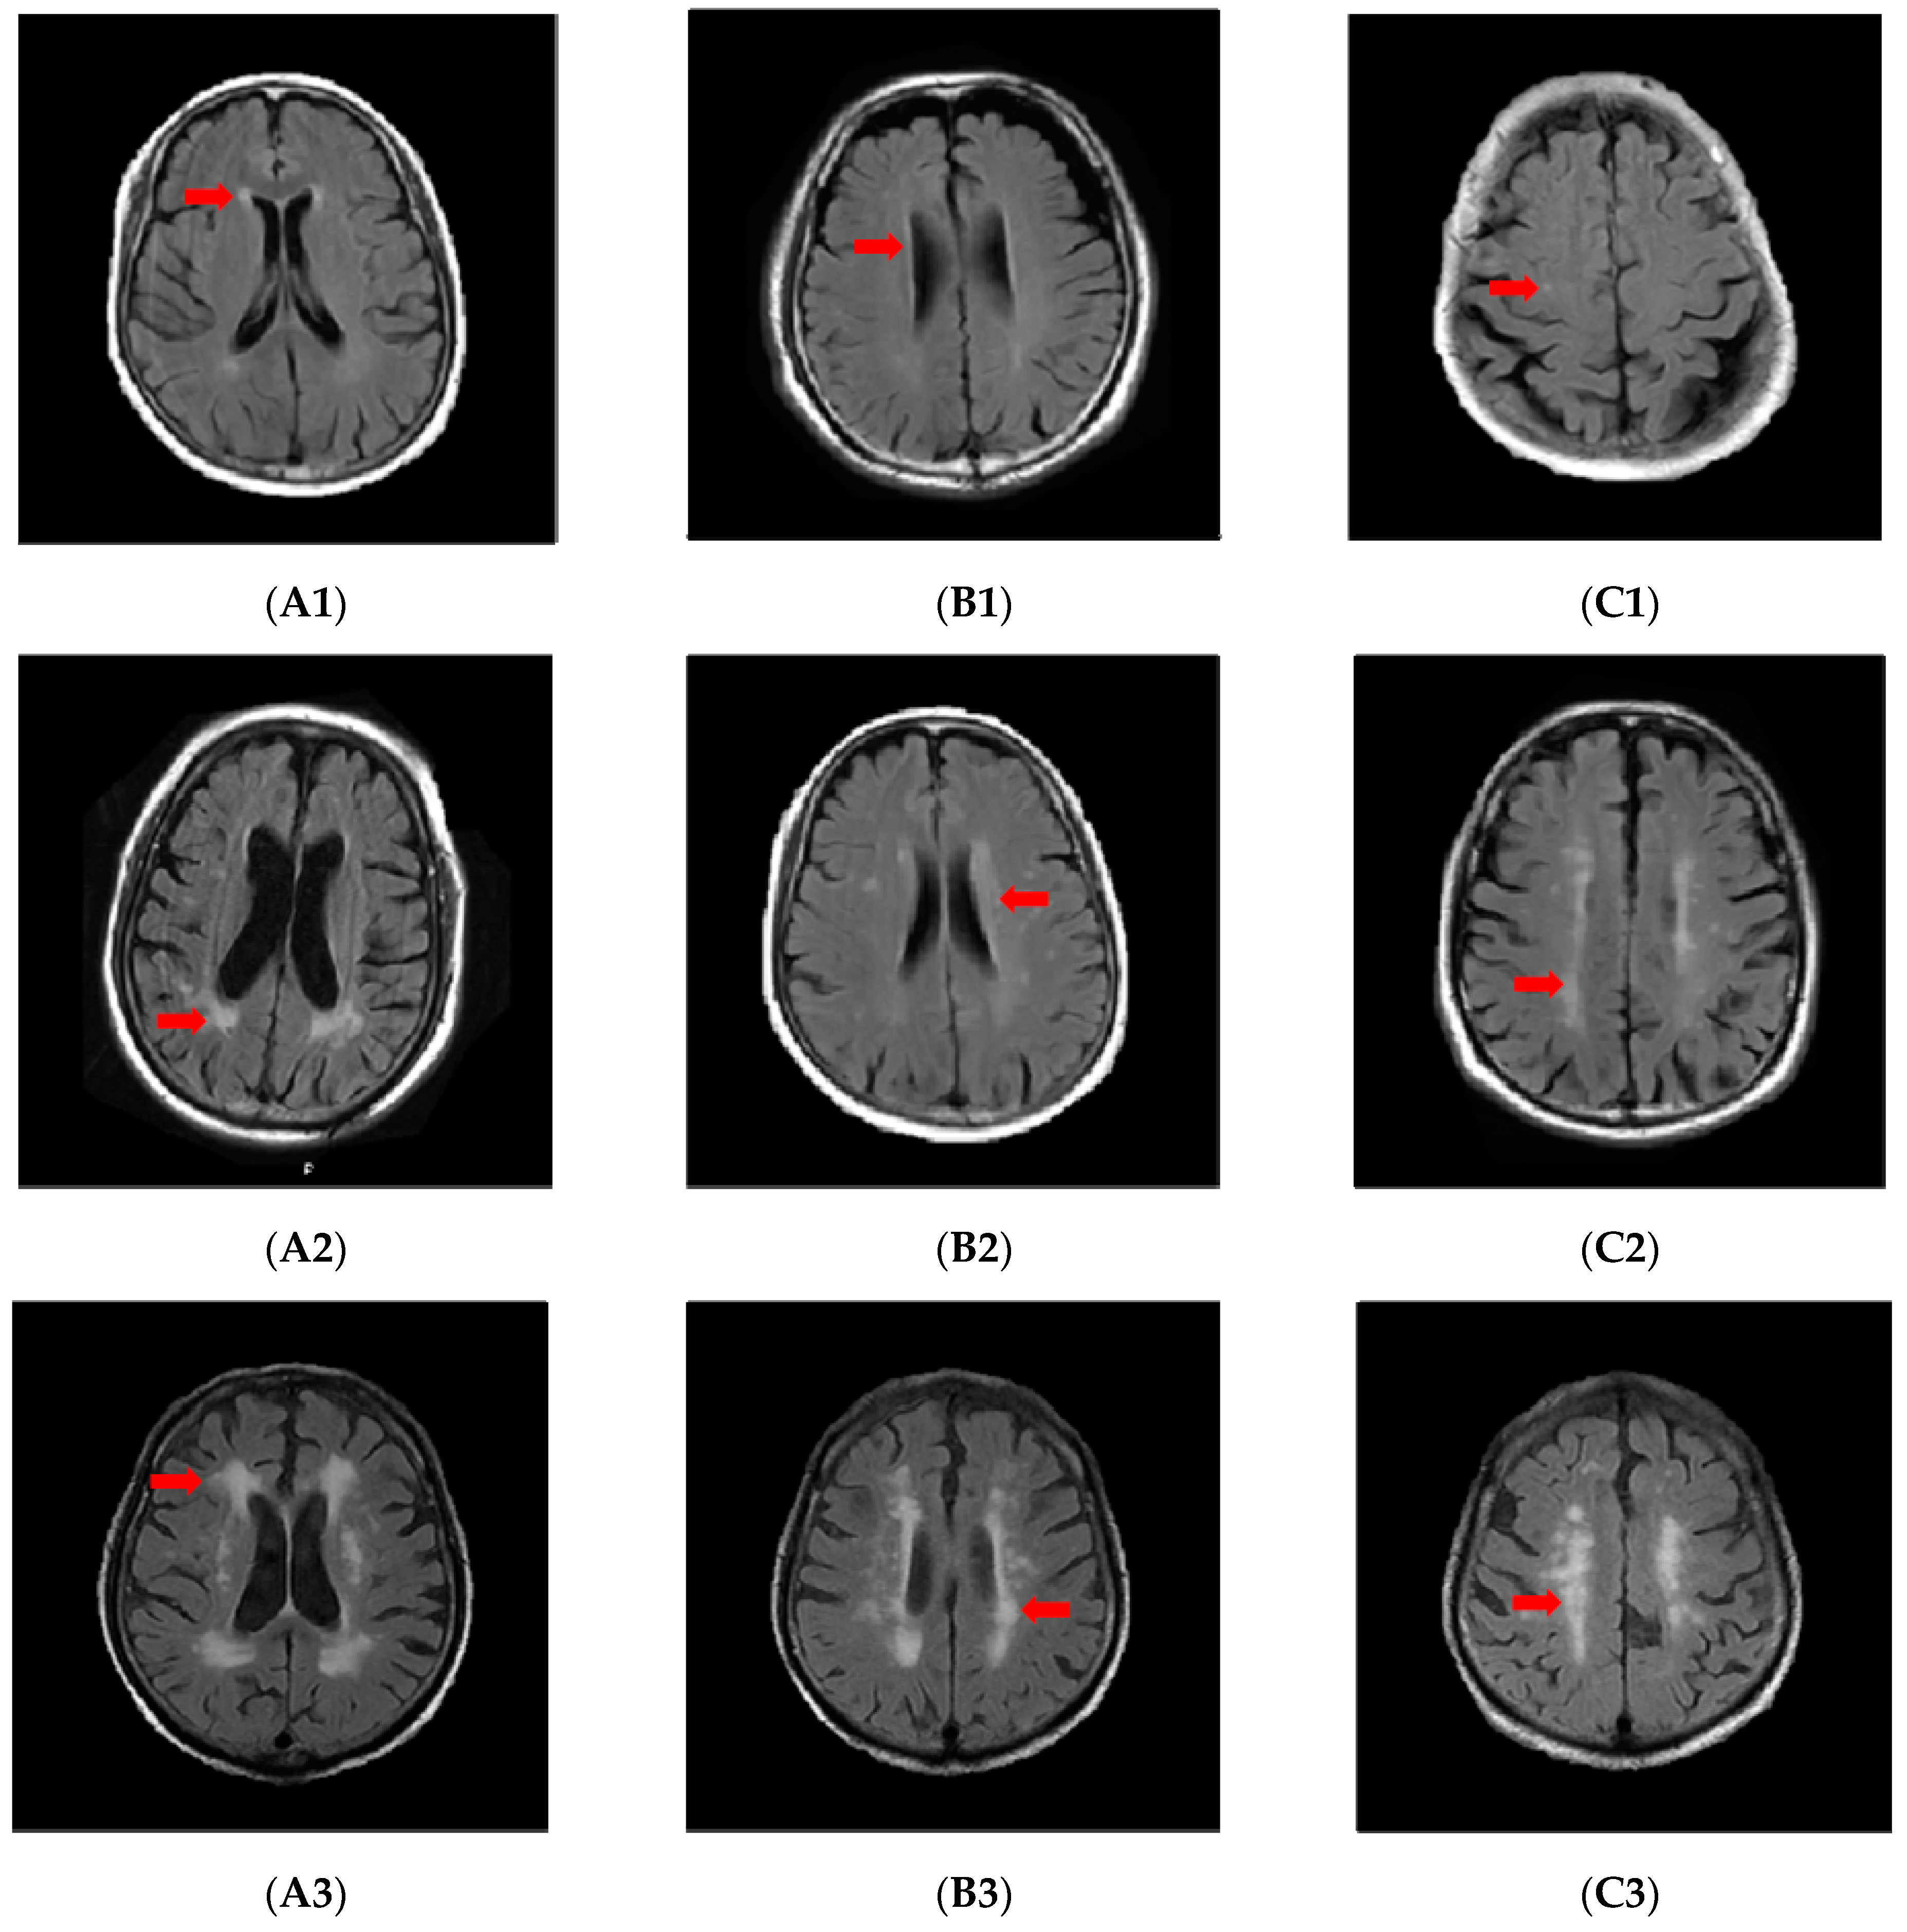

All patients’ MRI images were acquired in the Tongji hospital using a 1.5 Tesla MRI scanner. WMH is defined as the abnormal signal in the white matter region in MRI images, which manifested by high signal on T2 and FLAIR sequences and isointense or hypointense on T1 sequences. Fazekas score was used to classify the severity of WMH, and the scoring criteria are shown below (Figure 1). Periventricular white matter: 0 = none; 1 = cap or pencil-like thin lesion; 2 = smooth “halo”; 3 = irregular periventricular signal extending into deep white matter. Deep white matter: 0 = absent; 1 = single or multiple spots; 2 = beginning confluence; 3 = large areas of confluence. We defined a score of 0 as no WMH, 1 as mild, 2 as moderate, and 3 as severe. The more severe grade of periventricular white matter and deep white matter was taken as the severity of the overall WMH. Two experienced neurologists independently evaluated the MRI images with blind to any other information about the patient, and when disagreements occurred, a third neurologist was asked to make the final diagnosis.

Figure 1.

PWMH with Fazekas score of 1 (A1,B1); DWMH with Fazekas score of 1 (C1); PWMH with Fazekas score of 2 (A2,B2); DWMH with Fazekas score of 2 (C2); PWMH with Fazekas score of 3 (A3,B3); DWMH with Fazekas score of 3 (C3). The area indicated by the arrow in the figure is typical white matter hyperintensity. PWMH, periventricular white matter hyperintensity; DWMH, deep white matter hyperintensity.